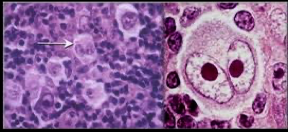

The diagnostic feature is the presence of malignant Reed-Sternberg cells (R-S cells), seen on lymph node biopsy.

- Large cell with two nuclei, looking like “owl eyes”